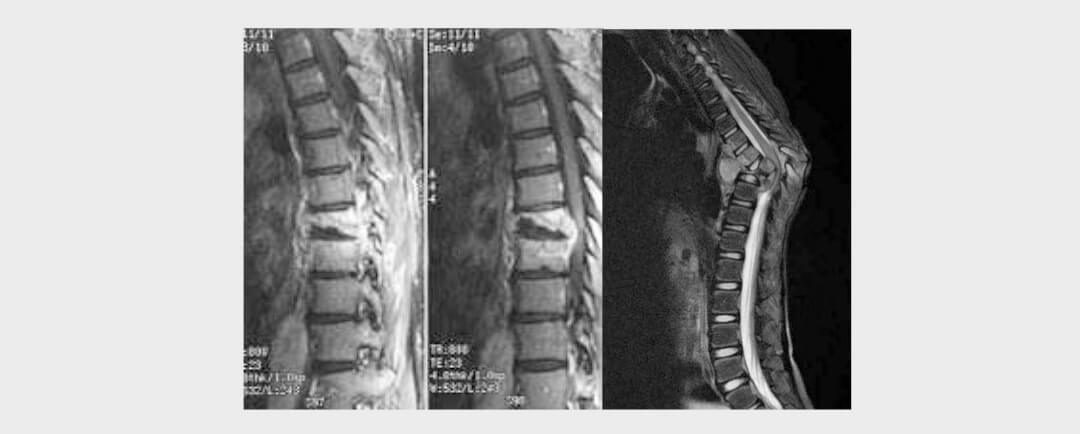

BRUCELLOSIS Y LUMBALGIA IntroducciónClínicaDiagnósticoImágenTratamiento BRUCELLOSIS Y LUMBALGIA Introducción BRUCELLOSIS Y LUMBALGIA (DOLOR EN ZONA LUMBAR DE COLUMNA) La brucelosis es un conocido padecimiento en México que se transmite a través de la digestión de...

por Dr. Esteban Castro | Feb 13, 2020 | Columna

HIDATIDOSIS VERTEBRALIntroducciónClínicaImágenDiagnósticoTratamiento HIDATIDOSIS VERTEBRAL Introducción La enfermedad conocida como hidatidosis es causada por la presencia del Echinococcus granulosus, el cual puede afectar a cualquier órgano del cuerpo, aunque el...